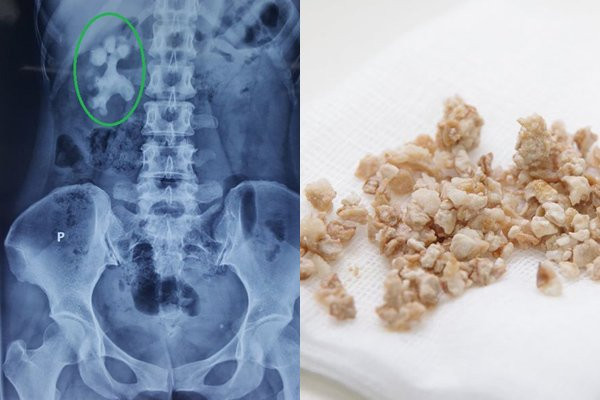

Những sai lầm trong ăn uống khiến nguy cơ mắc sỏi thận tăng cao

Nhiễm trùng đường tiết niệu, đau lưng, tiểu són, tiểu dắt, tiểu ra máu, đau đớn khi đi tiểu,… là những hậu quả do sỏi thận gây ra. Nguyên nhân sỏi thận lại đến từ chính những sai lầm trong ăn uống của nhiều người.

Uống ít nước khiến hệ tiết niệu ít việc, nước tiểu trở nên đậm đặc, dễ hình thành nên sỏi thận và sỏi đường tiết niệu. Ngược lại, nếu bạn uống đủ 2 lít nước mỗi ngày thì nước tiểu sẽ được làm loãng đồng thời có tác dụng rửa đường niệu đạo. Từ đó phòng được bênh sỏi thận và làm cho sỏi bài tiết ra ngoài.

Tiêu thụ nhiều thực phẩm giàu canxi

Nếu thừa canxi sẽ gây quá tải cho thận, nếu vẫn tiếp tục bổ sung quá nhu cầu cơ thể trong thời gian dài sẽ làm tăng nguy cơ sỏi niệu quản, sỏi thận. Canxi có trong thực phẩm dễ liên kết với oxalat trong ruột, từ đó gây nên sỏi canxi oxalat. Không chỉ có thực phẩm, việc tiêu thụ canxi trong bữa ăn cũng làm tăng nguy cơ mắc bệnh.

Ăn quá nhiều muối

Ăn quá nhiều muối khiến canxi không được tái hấp thu từ nước tiểu vào máu. Điều này làm cho canxi trong nước tiểu cao, có thể dẫn đến sỏi thận. Ăn ít muối giúp giữ lượng canxi trong nước tiểu thấp hơn. Canxi trong nước tiểu càng thấp thì nguy cơ hình thành sỏi thận càng thấp.

Ăn nhiều các thực phẩm giàu oxalat

Oxalat là một hợp chất tự nhiên có trong thực phẩm. Chúng liên kết với canxi trong nước tiểu để tạo thành sỏi thận. Những thực phẩm giàu oxalat bao gồm lúa mì, sản phẩm làm từ đậu nành, đậu phộng, củ cải, cà phê, khoai lang, socola, rau bina,… Vì vậy bạn nên hạn chế ăn những thực phẩm này.

Ăn nhiều đạm động vật

Ăn quá nhiều đạm động vật như hải sản, trứng, thịt gia cầm, thịt đỏ làm tăng nồng độ axit uric và có thể dẫn đến sỏi thận. Chế độ ăn giàu protein cũng làm giảm nồng độ citrate trong nước tiểu, chất hóa học trong nước tiểu giúp ngăn ngừa hình thành sỏi.